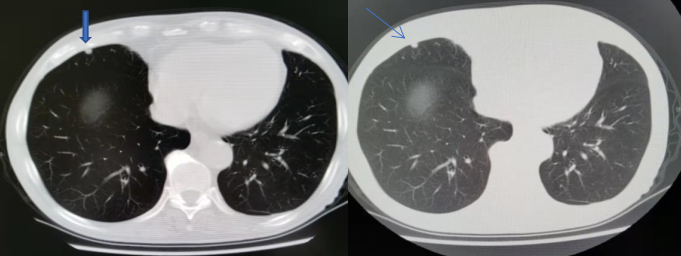

2022年1月胸部CT(图5):

右肺中叶切除术后,未见明显肿瘤复发征像;

右侧少量胸腔积液较前吸收;

右肺慢性炎症较前相仿;

双肺少许感染已吸收;

左肺下叶间裂处小结节同前,建议随访;

脂肪肝,肝脏小囊肿;

胃癌术后改变。

图5.胸部CT影像